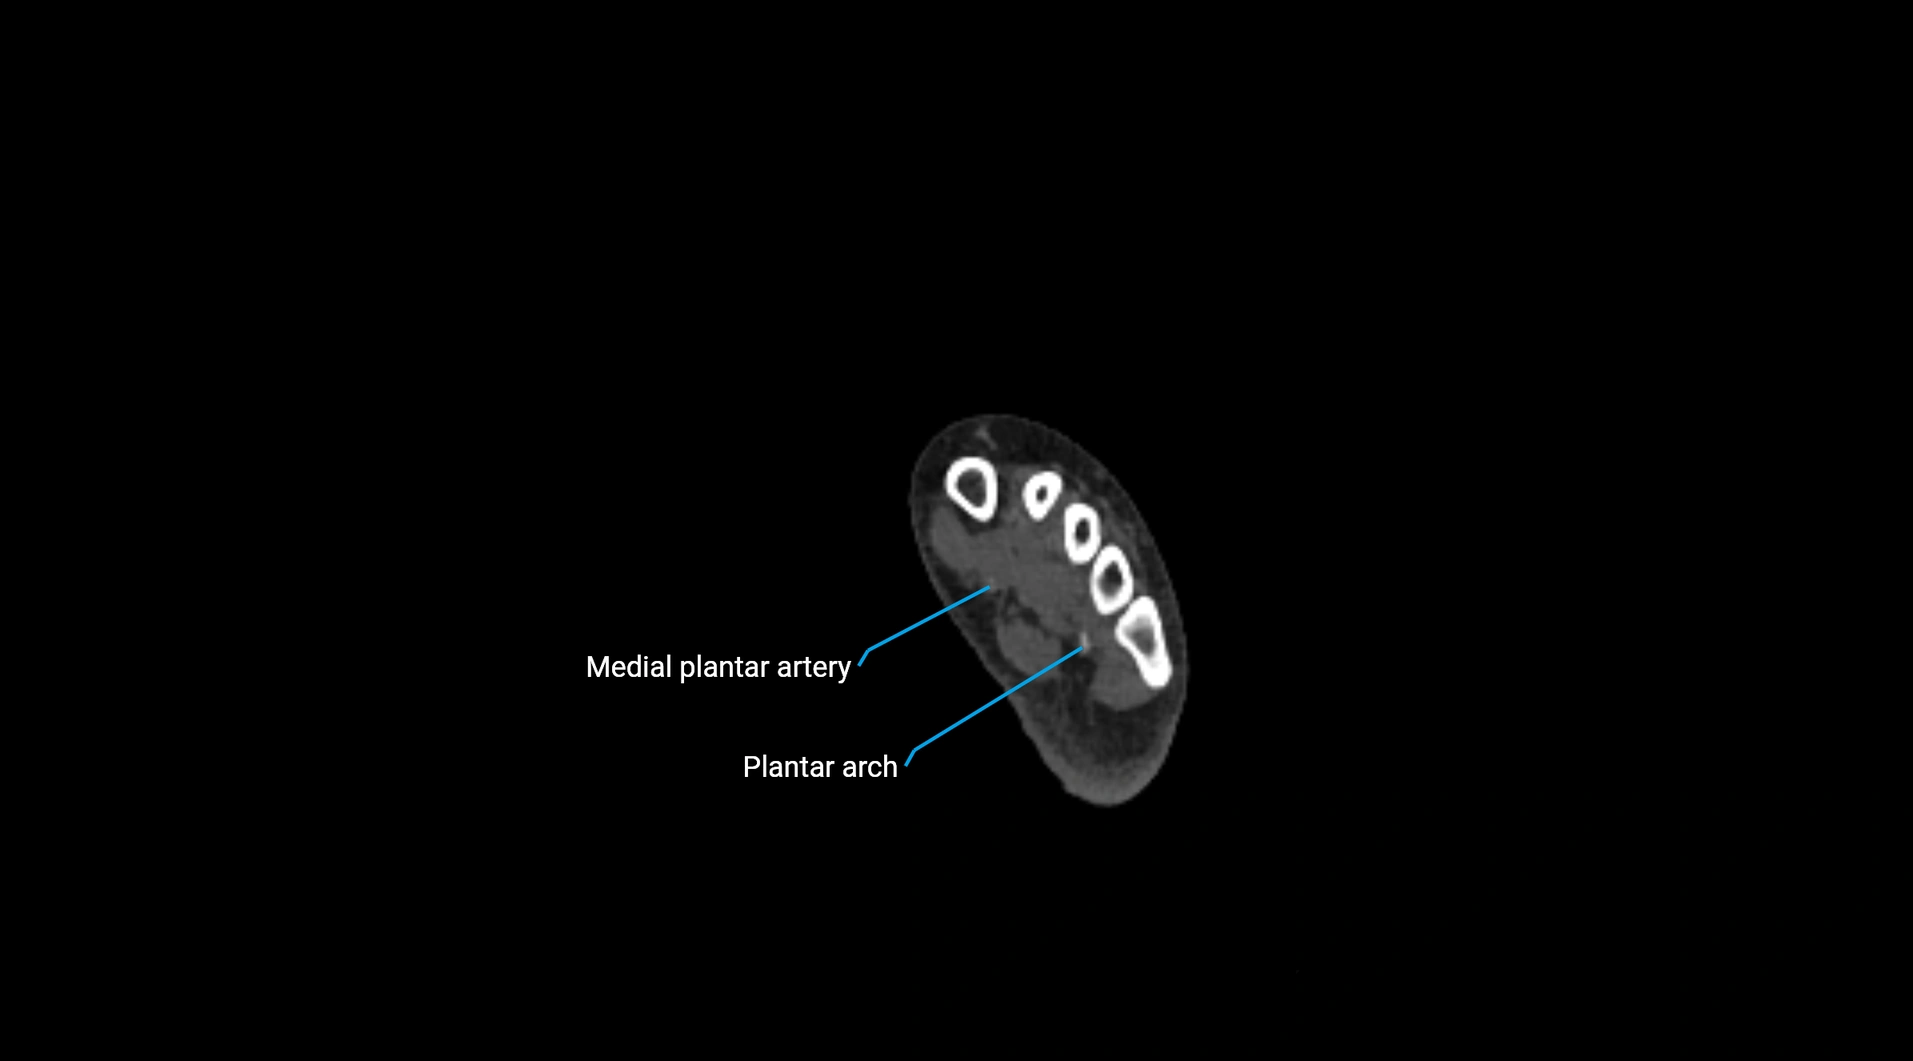

CT Appearance

Non-contrast CT:

• Appears as a tubular soft tissue structure anterior to vertebral bodies

• Calcified atherosclerotic plaques appear as hyperdense foci along the wall

• Useful for screening abdominal aortic aneurysm (AAA) size and mural calcification

Contrast-enhanced CT (CTA):

• Gold standard for abdominal aortic imaging

• Provides excellent detail of lumen, wall, aneurysm, thrombus, and branch vessels

• Multiplanar and 3D reconstructions help in aneurysm measurement, stent graft planning, and dissection evaluation

• Detects acute rupture, traumatic injury, or occlusion with high sensitivity